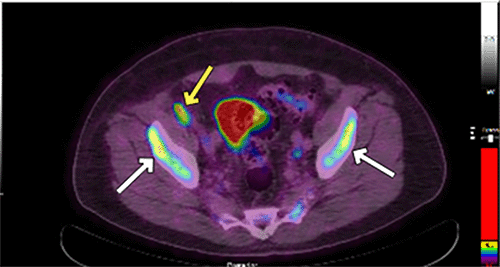

Bone marrow biopsy, performed as part of staging workup, revealed hypercellular marrow with reduced trilineage hematopoiesis and atypical B-cell infiltrates (Figure 2). Positron emission tomography (PET)/computed tomography (CT) scan identified mesenteric and external iliac lymphadenopathy along with focal bony involvement (Figure 3). The presence of atypical B-cell infiltrates in the bone marrow confirmed stage IV lymphoma by the Lugano classification.7

Figure 3. PET-CT Scan Findings. Published with Permission

A (coronal and sagittal views): Heterogeneous and focal fluorodeoxyglucose (FDG) uptake within the spinal column, indicating bony disease involvement (white arrows)

A (coronal and sagittal views): Heterogeneous and focal fluorodeoxyglucose (FDG) uptake within the spinal column, indicating bony disease involvement (white arrows). B (lower axial view): Lymphadenopathy (yellow arrow) in the mesenteric and external iliac regions alongside bony involvement of the pelvic bones (white arrows)